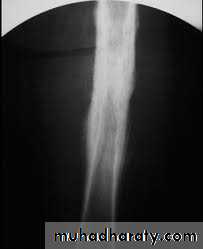

Primary malignant tumoursOsteosarcoma ( osteogenic sarcoma )

Ewing sarcoma

4.Periosteal reaction

the causes of localized peiosteal reactions adjacent to a lytic or sclerotic lesions are :

.Osteomyelitis.Malignant bone tumour , particularly Ewing sarcoma & osteosarcoma